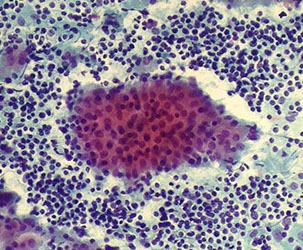

Pleomorphic adenoma

Pleomorphic adenoma (PA)

B9 mixed tumor, MCC salivary gland tumor (1/2-3/4 of all salivary gland neoplasms), painless, firm mass usually growing slowly in tail of parotid at jaw angle

Micro: fibromyxoid background, epithelial (round to columnar cells c uniform round nuclei grouped in honeycomb pattern with frayed edges) and myoepithelial / mesenchymal (myxoid ground substance-secreting single cells that can be spindly, clear, plasmacytoid or epithelioid) cells c chondromyxoid matrix (looks blue like mucin / troll hair) and sometimes tyrosine crystals

- matrix component can be little or appear adenoid cystic

- 1/5 have atypia or metaplasia

Genes: (+) PLAG1 gene alterations pathognomonic

PA

PA - trolls hair